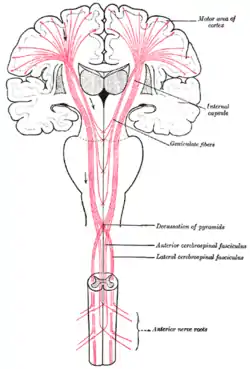

Spinal cord tracts, with pyramidal tracts labeled at upper left | |

Superficial dissection of brain-stem. Ventral view. The motor tract.

The motor tract.